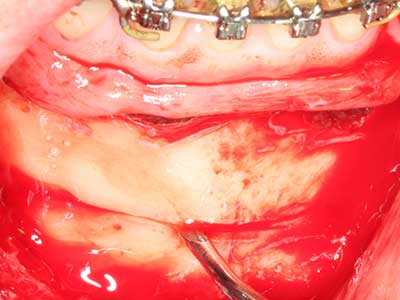

Piezosurgery has additional advantages when harvesting bone blocks. In addition to the high precision with osteotomy described above, the use of the thin saw tips specifically minimizes loss of material. Greater loss of material during harvesting can be expected with the thicker instrument tips, particularly when using Lindemann drills (Lakshmiganthan, Gokulanathan et al. 2012). The basal separation, which is necessary particularly for retromolar block transplants, is simplified by specially designed rectangular saws, with the result that piezosurgery is viewed as a precise, simple and safe procedure for harvesting retromolar bone blocks (Happe 2007) (Fig. 1-12).